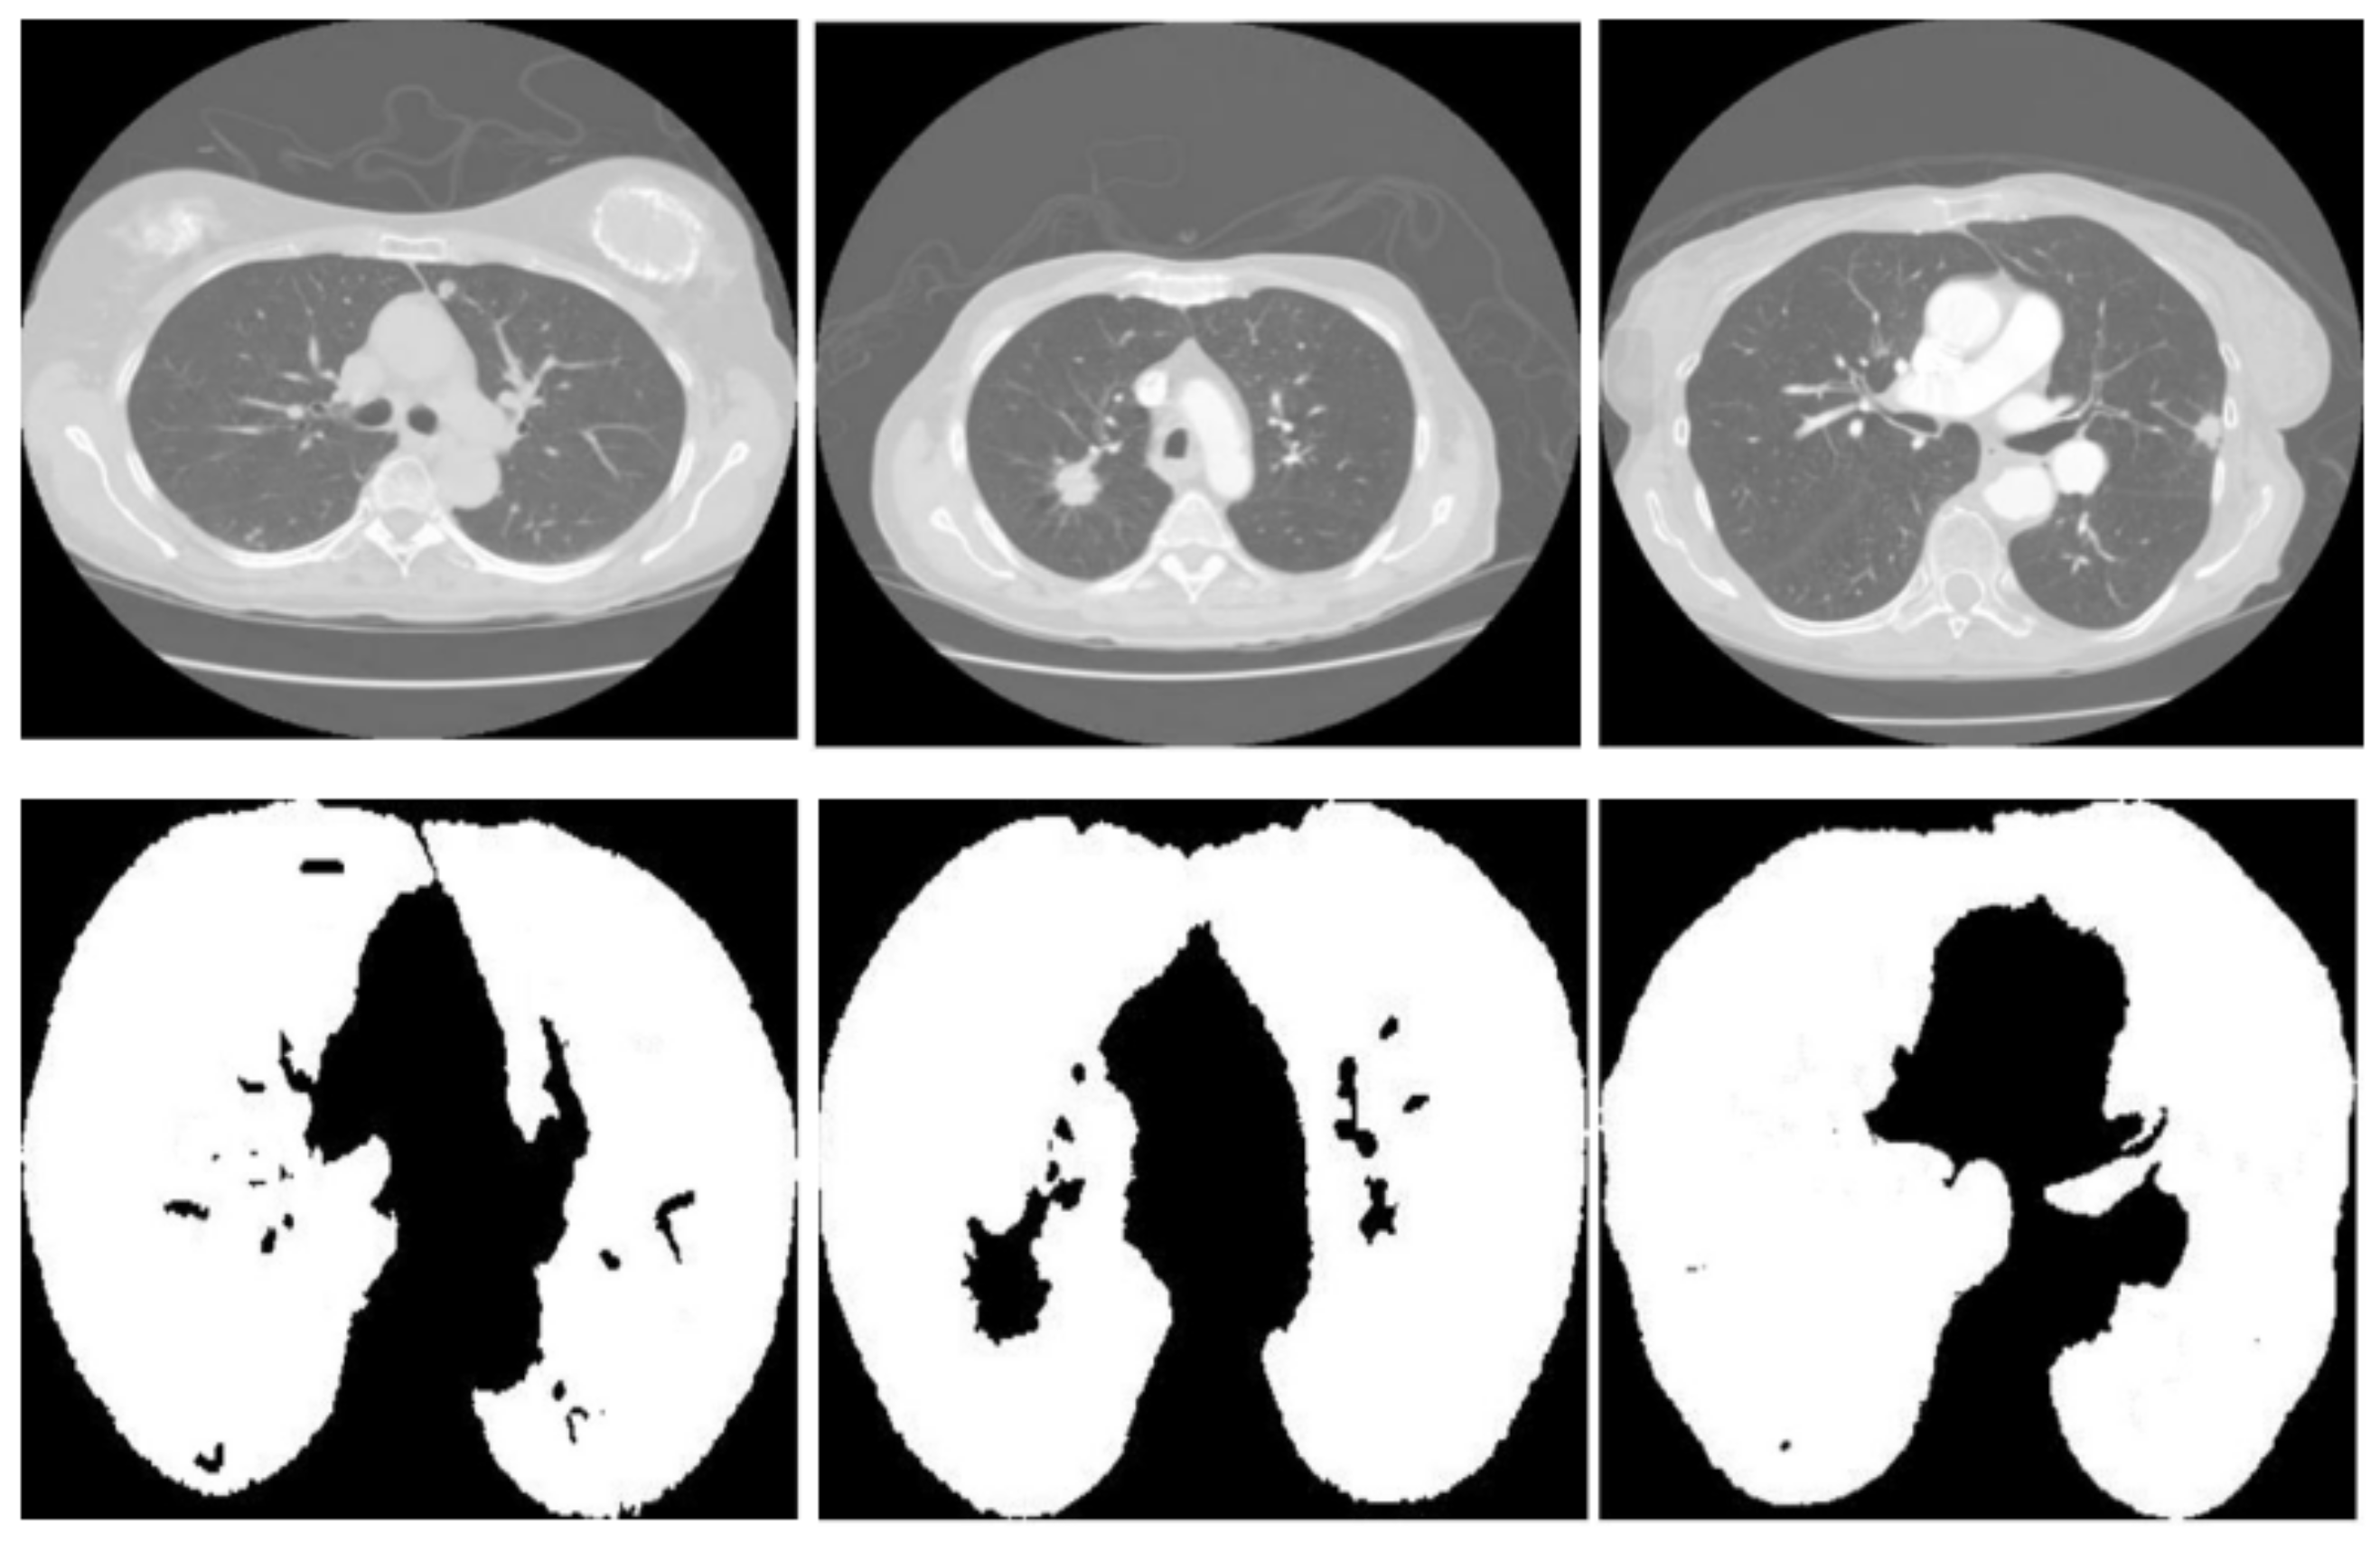

Figure 3 displays three sets of images produced by the proposed lung segmentation model. The top row illustrates the original CT scans from patients, depicting cross-sectional images of the thoracic cavity. These scans provide a clear view of the lung structures, bones, and surrounding tissues, with radiodensity variations allowing these components’ differentiation. In the corresponding images of the bottom row, the results of the segmentation model are evident. Here, the lung regions have been delineated and filled in, starkly contrasting with the non-lung areas, which appear as black space. The segmentation model seems to have successfully extracted the lung regions from the CT images with high accuracy. In the first column, the model accurately identifies the lung boundaries and the separation between the left and right lungs. The second column shows a similarly precise segmentation, with the model correctly excluding the heart and the spine, which are centrally located in the thoracic cavity. In the third column, despite the more complex lung structures due to either a pathological condition or a scanning artifact, the model has managed to delineate the lung region, preserving the intricate details and the shape of the lungs.

Figure 3.

Comparative visualization of original CT scans and segmented lung regions by the proposed model.